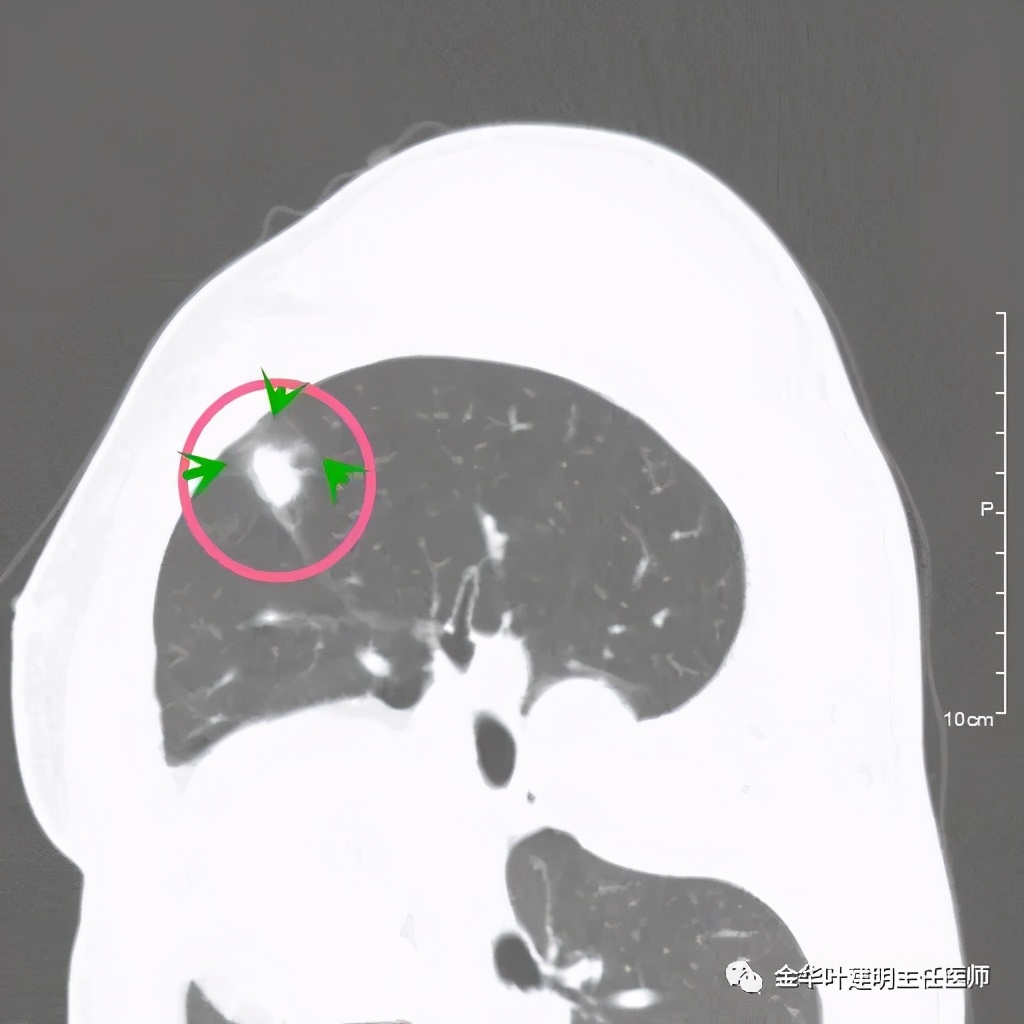

病灶实性,但收缩力弱,绿色箭头示病灶边缘有一圈晕征(模糊且均匀)

病灶实性,但收缩力弱,没有细毛刺征,实性部分比较圆润,绿色箭头示病灶边缘有一圈晕征(模糊且均匀)